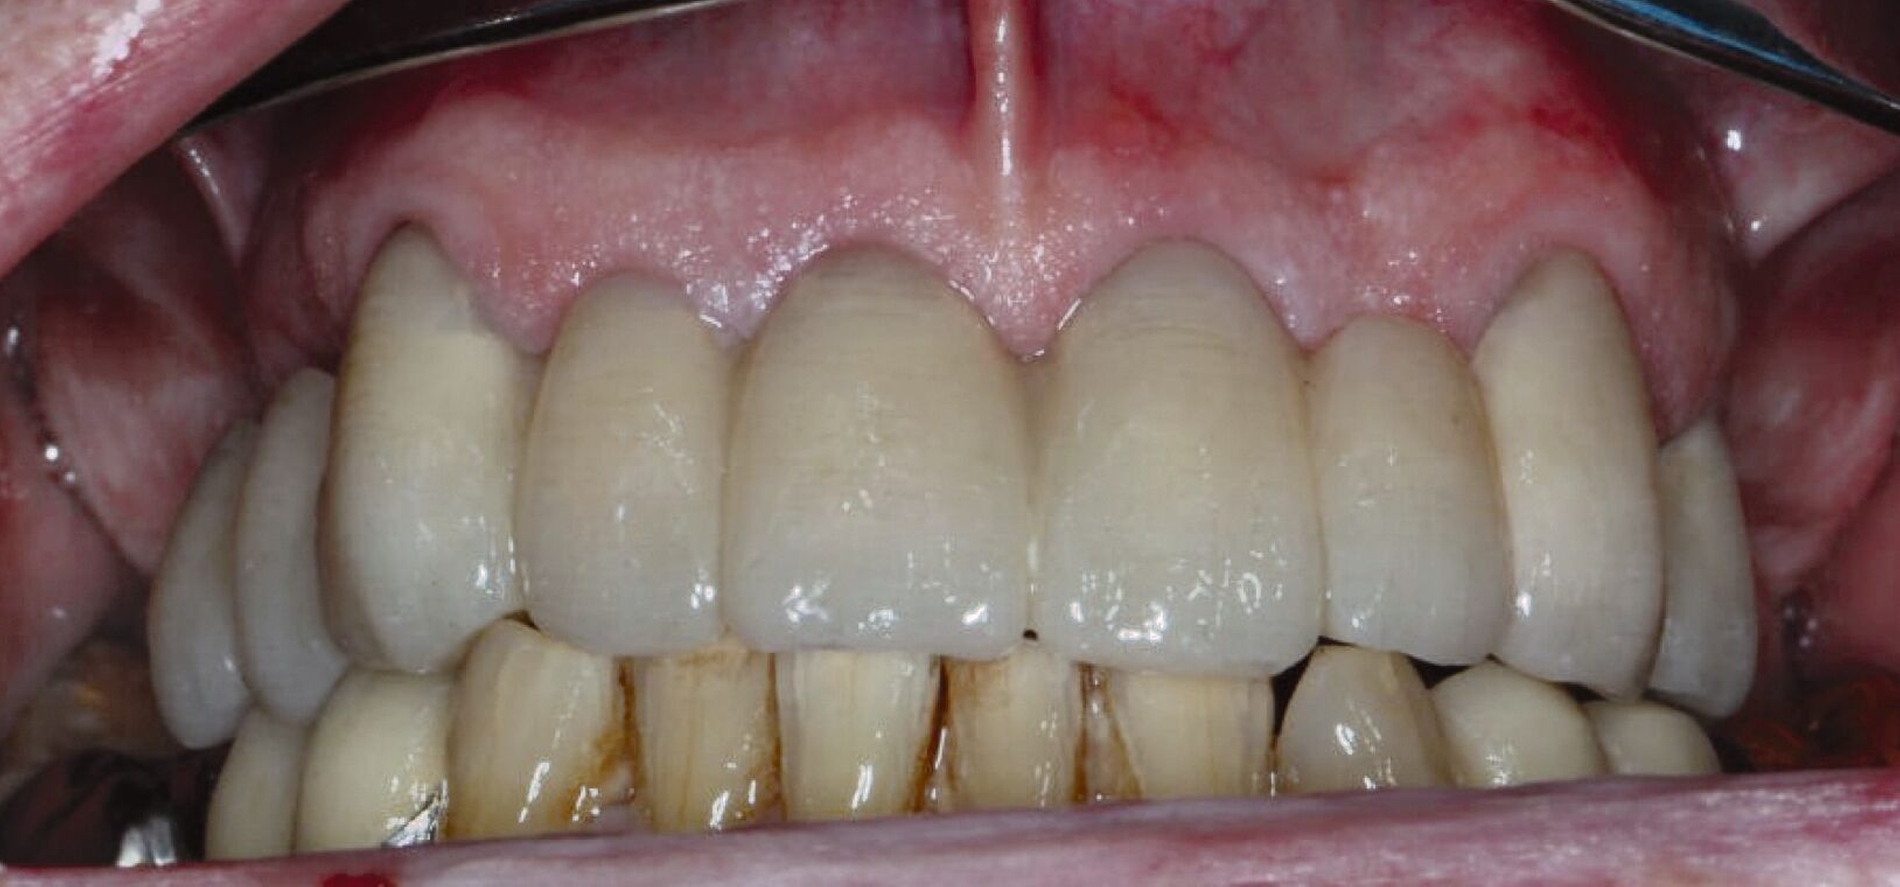

Der Patient stand unter der Dauermedikation von Metformin 500 mg, Ramipril 5 mg, Torasemid 10 mg, Metohexal 47,5 mg, Simvastatin 20 mg, Tamsulosin 0,4 mg und 3 mg Marcumar (INR 2,5–2,8) bei Zustand nach einer Bypass-Operation im Jahr 2019. Klinisch zeigten sich im Oberkiefer insuffiziente, verblockte und verblendete NEM-Kronen mit beidseitigen Gold-Extensionen distal, die über Geschiebe mit dem anterioren Anteil verschraubt waren (Abbildungen 1 und 2). Der Patient berichtete, dass die vorhandenen Kronen und Brücken 1984 eingesetzt worden seien.

Übergangsweise wurden die verbliebenen Stümpfe mit einem festsitzenden Langzeitprovisorium aus einem Hochleistungspolymer der PET-Gruppe versorgt (Abbildung 4), um Stabilität über einen längeren Zeitraum gewährleisten zu können. Nach der Extraktion des Zahnes 14 und der Abheilung der Extraktionswunde wurde der Patient über die Optionen des definitiven Zahnersatzes aufgeklärt:

Schließlich erfolgte die Eingliederung der fertigen Teleskopprothese (Abbildung 6). Die Primärteile wurden mit Glasionomerzement auf den Stümpfen zementiert. Nach Entfernung der Zementreste und der erneuten Überprüfung der statischen und der dynamischen Okklusion, ist das gemeinsame Üben des Ein- und Ausgliederns der Prothese gerade bei dieser Art der Arbeit unabdingbar. Eine ausführliche Aufklärung über die Reinigung, Handhabung und das Recall folgte.

Nach Durchführung einer dentalen Volumentomografie (DVT) wurden daher zahnärztliche Implantate in Regio 14, 15 und 25 im Sinne einer verkürzten Zahnreihe geplant und inseriert (Abbildung 7). Nach dreimonatiger subgingivaler, konventioneller Einheilzeit wurden die Implantate freigelegt. Zwei Wochen später begann man die vorhandenen Primärkronen zu entfernen. Die Stümpfe wurden nachpräpariert und es wurden erneut Fäden gelegt (Abbildung 8a und 8b).

Nachdem die Einheilkäppchen entfernt und die Scanbodies in die Implantate eingeschraubt wurden, erfolgte der Intraoralscan (Abbildung 8c). Der festsitzende Zahnersatz wurde im zahntechnischen Labor designt und aus monolithischem Zirkonoxid gefräst. Die Kronen konnten schließlich selbstadhäsiv auf den Stümpfen befestigt werden. Das Einschrauben der Implantatkronen erfolgte mit Drehmomentschlüssel auf 35 Ncm nach Herstellerangabe. Die Schraubkanäle wurden anschließend verschlossen. Mit dem Endergebnis (Abbildung 8d) zeigte sich der Patient auch im Recallverlauf hochzufrieden.